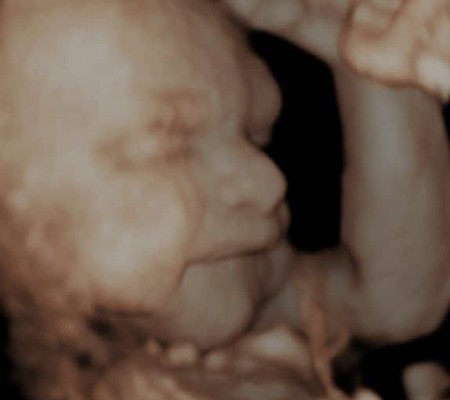

3D i 4D tehnologija omogućava da vidimo površinu bebe na lepši način i pokrete ploda u realnom vremenu.

Takođe nam omogućava da bolje vidimo fetalne mane na licu, šakama i stopalima.

Kao i 2D, 3D i 4D koriste ultrazvučni talas da se kreira slika bebe u materici. 3D je kreirana slika u prostoru dok 4D prikazuje pokret unutar materice pa možemo videti kako se beba smeje, mršti ili zeva.

Za prikaz ovih preseka potrebni su odgovarajući uslovi kao što su položaj ploda (lice ka nama), normalna količina plodove vode, poželjno je da ruke, noge i pupčanik ne budu ispred bebinog lica. U neodgovarajućim uslovima ovaj snimak nije moguće napraviti.

Da bi se dobile dobre slike poželjno je da se pregled radi između 24 i 32 nedelje trudnoće.